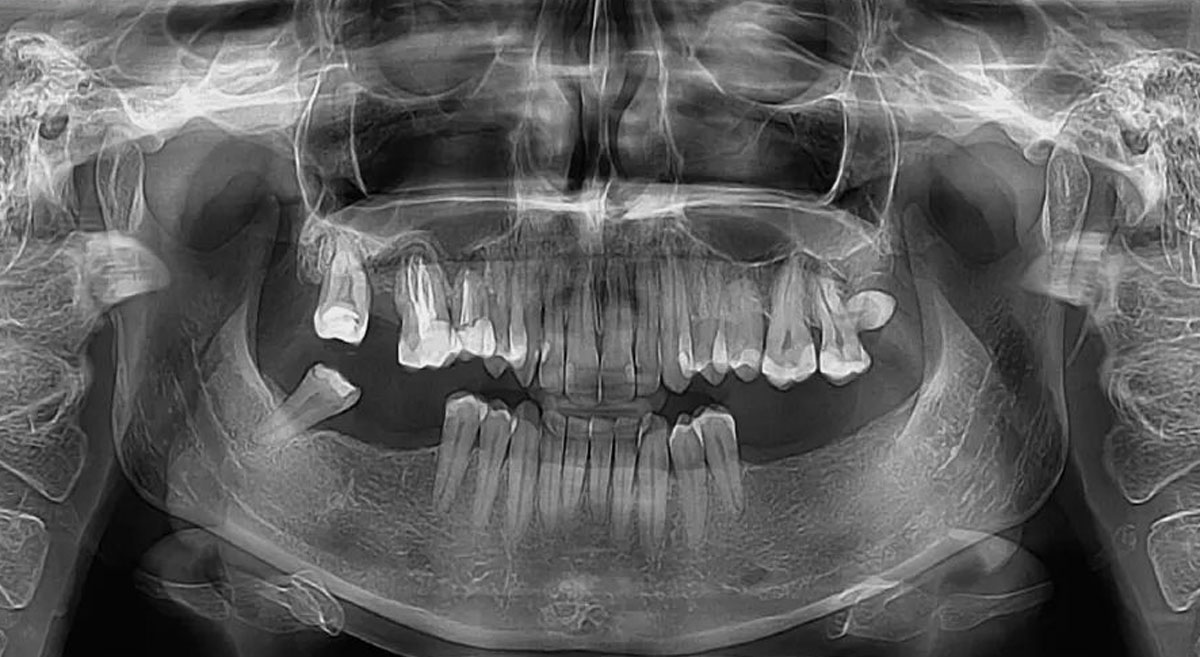

Stručno rečeno, ortopan predstavlja panoramsko snimanje vilica u ortoradijalnoj projekciji. Specifičnost ove metode je u tome što je centralni snop x-zraka tokom celog procesa upravan na ravan vilica.

Dok se rendgenska cev kreće iza glave pacijenta po putanji parabole, digitalni senzori sinhrono beleže podatke ispred glave. Rezultat je savršen prikaz:

- Kompletne donje vilice sa zglobnim glavicama (kondilima).

- Maksilarnih sinusa (posebno alveolarnih recesusa).

- Gornje vilice sa svim pripadajućim zubima.

- Regije pljuvačnih žlezda.

- Ortopan (ortopantomografija) – panoramska 2D radiografska tehnika koja u jednom snimku prikazuje obe vilice, sve zube i korenove, vilične zglobove i okolne koštane strukture.